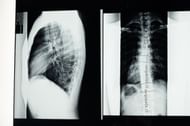

Tarlov cysts can be challenging to diagnose as they may not cause any symptoms, and their appearance on MRI scans may be similar to other spinal abnormalities.

A detailed medical history, physical examination, and imaging tests, such as MRI or CT scans, may be used to diagnose perineural cysts.